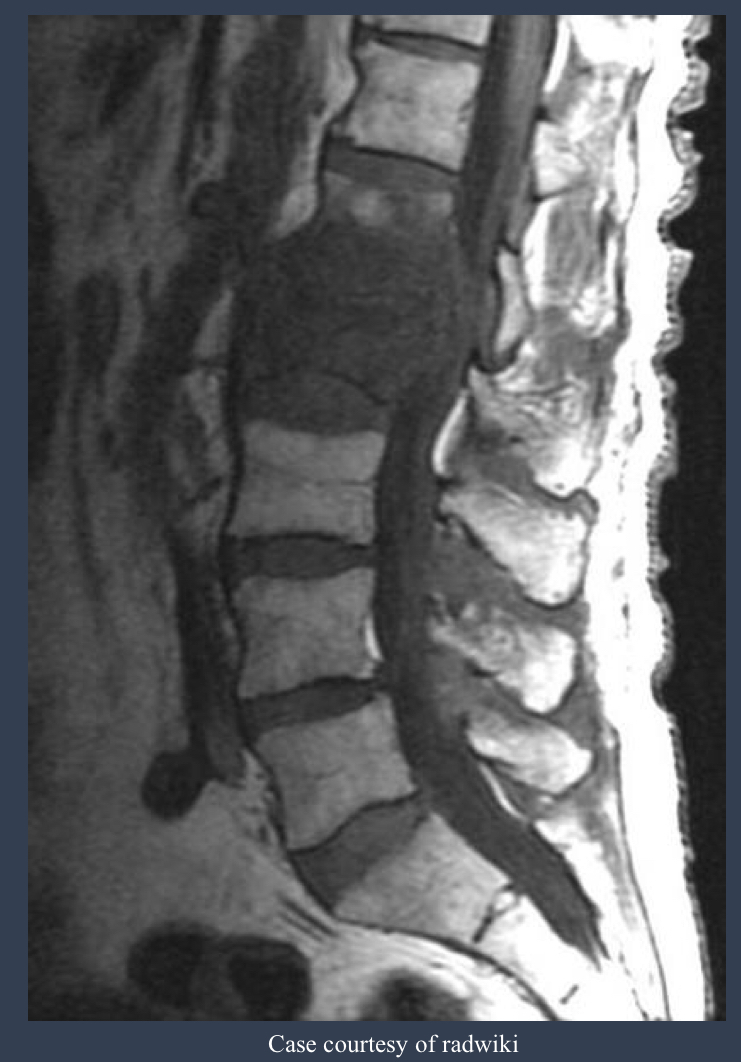

what is this?

spondylodiscitis

how is this spread?

hematogenously

what is this imaging modality?

what is this condition? why?

MRI and T1 weighted CSF/bone is dark and fat appears bright

tubercular spondylitis “Pott’s Disease”; ???